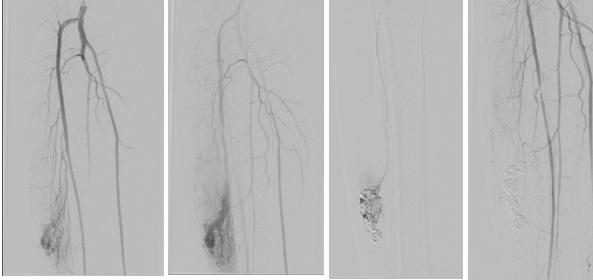

手术在全麻下进行,在郭教授和刘教授指导下首先同侧顺穿股动脉后置鞘造影,结果显示患者右小腿动静脉畸形学工丰富,供血动脉来自胫前动脉,“瘤巢”显影染色后回流至增粗迂曲的回流静脉(图1)。之后同侧逆穿股静脉并置鞘,引入微导管到达回流静脉的远心端,释放多枚可控弹簧圈栓塞回流静脉,减慢回流后再注射无水乙醇以硬化“瘤巢”,最终动脉端造影显示病灶染色消失,效果满意。术后,郭教授会诊了1例复杂K-T综合征的患儿,提出了合理诊疗方案。